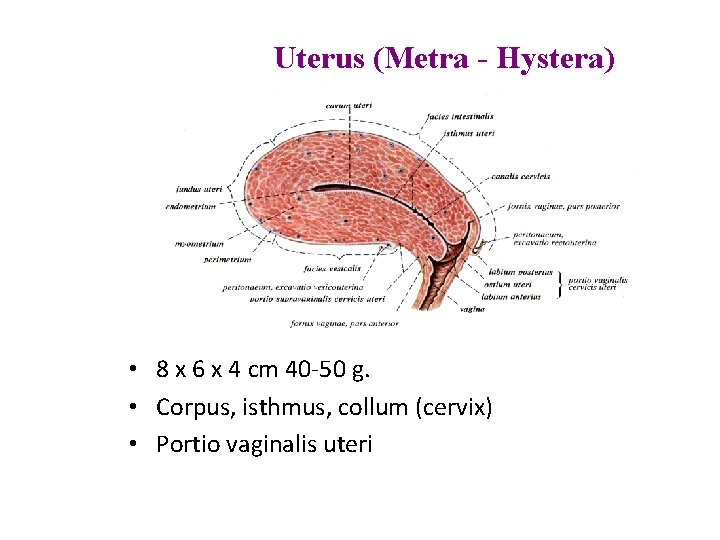

Uterus (Metra - Hystera) • 8 x 6 x 4 cm 40 -50 g. • Corpus, isthmus, collum (cervix) • Portio vaginalis uteri